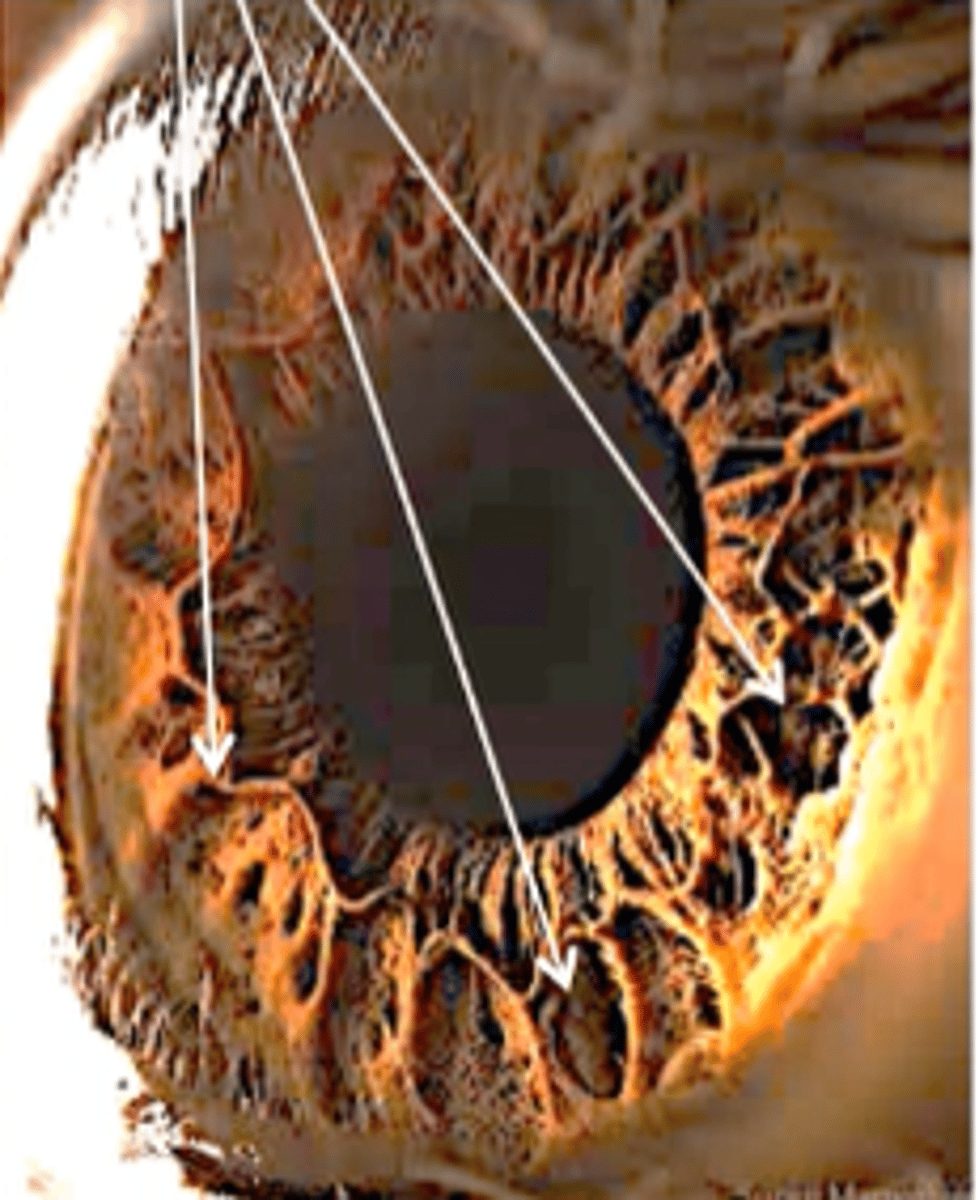

What is the collarette of the iris?

- anatomical border between pupillary and ciliary region of the iris, thickest region

- site of the minor arterial circle

What are the holes in the anterior border layer of the iris?

Crypts of Fuchs

What is the purpose of the Crypts of Fuchs?

allow aqueous to enter stroma, serve as "iris fingerprint"